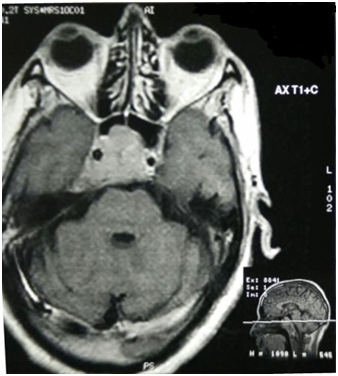

A 62 years old male presented to neurosurgery with a two month history of drooping of right eye lid, generalised body weakness and severe headache. Examination was significant for right sided ptosis and diplopia. History was unremarkable with no significant past illness and there was no clinical evidence of icterus, hepatomegaly or significant abdominal distension. Routine initial investigations including complete blood counts, liver and renal function tests were normal. Subsequently, an MRI brain was done, which was suggestive of a pituitary macroadenoma, showing lobulated mass in the sellar and infrasellar region involving the sphenoid and clivus, with intracerebral bleed compressing the right 3rd cranial nerve (Figure 1). Subsequently, endoscopic decompression and biopsy were performed. The procedure revealed a highly vascular and invasive tumor eroding the sella and sphenoid sinus, suggestive of an invasive macroadenoma.

Figure 1 Contrast enhanced MRI showing enhancing lesion in the sella.